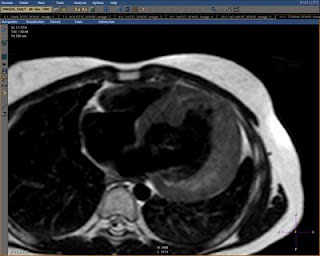

艾米丽在2007年6月被诊断出患有肥厚性心肌病(什么是肥厚性心肌),虽然大部分的肥厚性心肌病类型都是较为稳定的,但是艾米丽的不同,随时可能心脏衰竭而亡。下图就是艾米丽的心脏核磁共振成像: